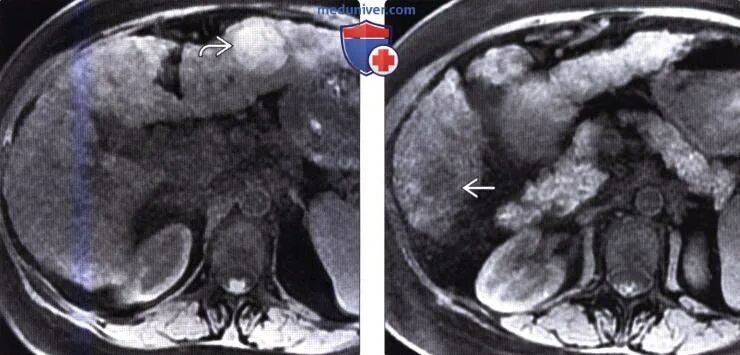

Очаги регенерации